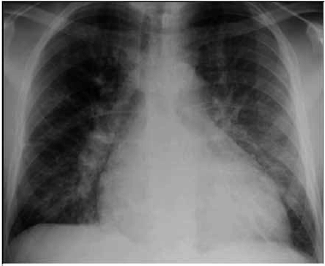

Paciente do sexo masculino, 57 anos de idade, acompanhado pela esposa, procurou serviço de urgência por dispneia aos pequenos esforços, edema de membros inferiores, diminuição do volume urinário, tosse seca associada a dispneia progressiva. Os sintomas se iniciaram há, aproximadamente, 6 meses, com dispneia seguida de edema. A dispneia, que era aos esforços moderados, rapidamente progrediu até estar presente no repouso. À ausculta pulmonar apresentou roncos e estertores em bases pulmonares. Ao raio X apresentou a radiografia a seguir:

(Arquivo pessoal, imagem usada com autorização)

Com base nas informações apresentadas no caso clínico e na imagem, qual conduta inicial mais adequada?

Paciente do sexo masculino, 57 anos de idade, acompanhado pela esposa, procurou serviço de urgência por dispneia aos pequenos esforços, edema de membros inferiores, diminuição do volume urinário, tosse seca associada a dispneia progressiva. Os sintomas se iniciaram há, aproximadamente, 6 meses, com dispneia seguida de edema. A dispneia, que era aos esforços moderados, rapidamente progrediu até estar presente no repouso. À ausculta pulmonar apresentou roncos e estertores em bases pulmonares. Ao raio X apresentou a radiografia a seguir:

(Arquivo pessoal, imagem usada com autorização)

Ao exame físico, apresentou-se ansioso, agitado, dispneico, taquipneico, com frequência respiratória (FR) de 36 ipm, pressão arterial (PA) de 200/118 mmHg, frequência cardíaca (FC) de 104 bpm, temperatura (T) de 36,8 °C, saturação periférica de oxigênio (SpO2) de 88% com cateter nasal 3 L/min de oxigênio. Coletada gasometria arterial: pH: 7,16; PO2: 70; PCO2: 65; HCO3: 23; BE: –2. Considerando esses dados, o caso clínico e a imagem apresentados, assinale a alternativa correta quando ao provável diagnóstico.

Paciente do sexo masculino, 57 anos de idade, acompanhado pela esposa, procurou serviço de urgência por dispneia aos pequenos esforços, edema de membros inferiores, diminuição do volume urinário, tosse seca associada a dispneia progressiva. Os sintomas se iniciaram há, aproximadamente, 6 meses, com dispneia seguida de edema. A dispneia, que era aos esforços moderados, rapidamente progrediu até estar presente no repouso. À ausculta pulmonar apresentou roncos e estertores em bases pulmonares. Ao raio X apresentou a radiografia a seguir:

(Arquivo pessoal, imagem usada com autorização)

Qual o provável diagnóstico de acordo com o caso clínico e com a imagem apresentados?